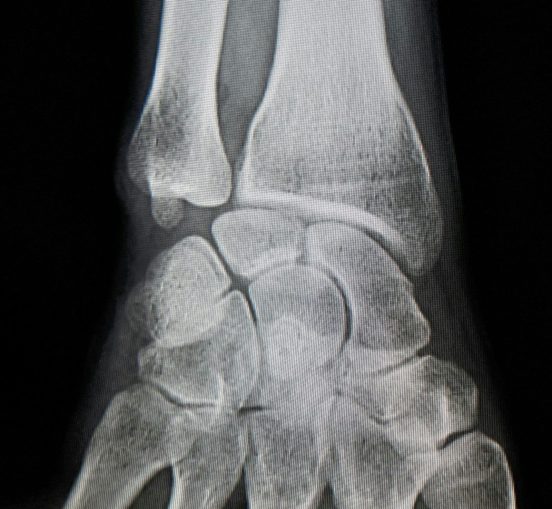

Posición del escafoides en la muñeca